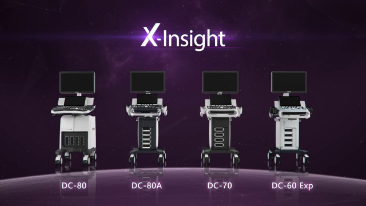

A solu??o totalmente nova da Mindray Ă© uma excelente transforma??o da vis?o permanente do cliente com base nas suas necessidades clĂnicas, combinada Ă s mais altas tecnologias de ultrassom em desenvolvimento.

O DC-70 com X-Insight, p?e o foco onde realmente importa e ajuda vocĂȘ a gerenciar as prĂĄticas clĂnicas diĂĄrias com facilidade e rigor.

Com base em uma profunda vis?o das necessidades do cliente, o DC-70 com X-Insight foi desenvolvido para oferecer diagnĂłsticos por imagens de alta eficiĂȘncia e com precis?o, o que Ă© possĂvel gra?as Ă Nitidez eXclusiva, InteligĂȘncia eXcepcional, eXceeding Experience.